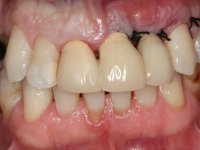

Endodontic treatments were performed and a metalic non screwed intra radicular post was placed on tooth 1.1. An alginate impression was made for laboratory confection of a reinforced acrylic provisional bridge, with teeth 1.1 and 2.2 as abutments and 2.2 as a pontic. After preparation of tooth 1.1 and root preparation of 2.1, the bridge was relined in mouth with self-polymerizable acrylic using a metal post for further retaining the prepared root canal on 2.1. Tooth 2.2 was cut at the gingival level to function as support. In the same session, the impression of the root canal of the 2.1 was made for the laboratory confection of a cast post and core. A double mixture technique with plastic tutor was used after previous canal vaseline with endodontic file and cotton. The provisional bridge was provisionally cemented and the cast post and core was made in the laboratory. Cast post and core cementation was made with resin-reinforced glass ionomer cement and the provisional bridge had to be readjusted to the new situation by removing the post at the site of 2.1. After careful surgical planning, a dental implant was placed, simultaneously with extraction of the root of tooth 2.2. The provisional bridge was placed by resting on the healing screw placed in the implant. The respected osteointegration period was 12 weeks, during which the provisional bridge was relined twice. After complete maturation of hard and soft tissues, definitive impressions were made. The gingival retraction technique was applied with an impregnated retraction cord and impression was performed using double mixture, open tray impression technique. A custom precious metal abutment implant was prepared in the lab, along with 3 metal caps to be used as infrastructures for the metal ceramic crowns. Particular care was taken in the confection of the cervical finishing line of the implant abutment, in order to follow the soft tissues emergence profile. Proof of infrastructures was done in the mouth being evaluated clinically and imagiologically. Collection of color information was done by the ceramist at the office. Ceramic was applied in the laboratory and the finished work was placed in the mouth after approval by the patient. Definitive cementation was made with resin-reinforced glass ionomer cement, and the first crown to be cemented was that of the implant, to facilitate removal of the excess.